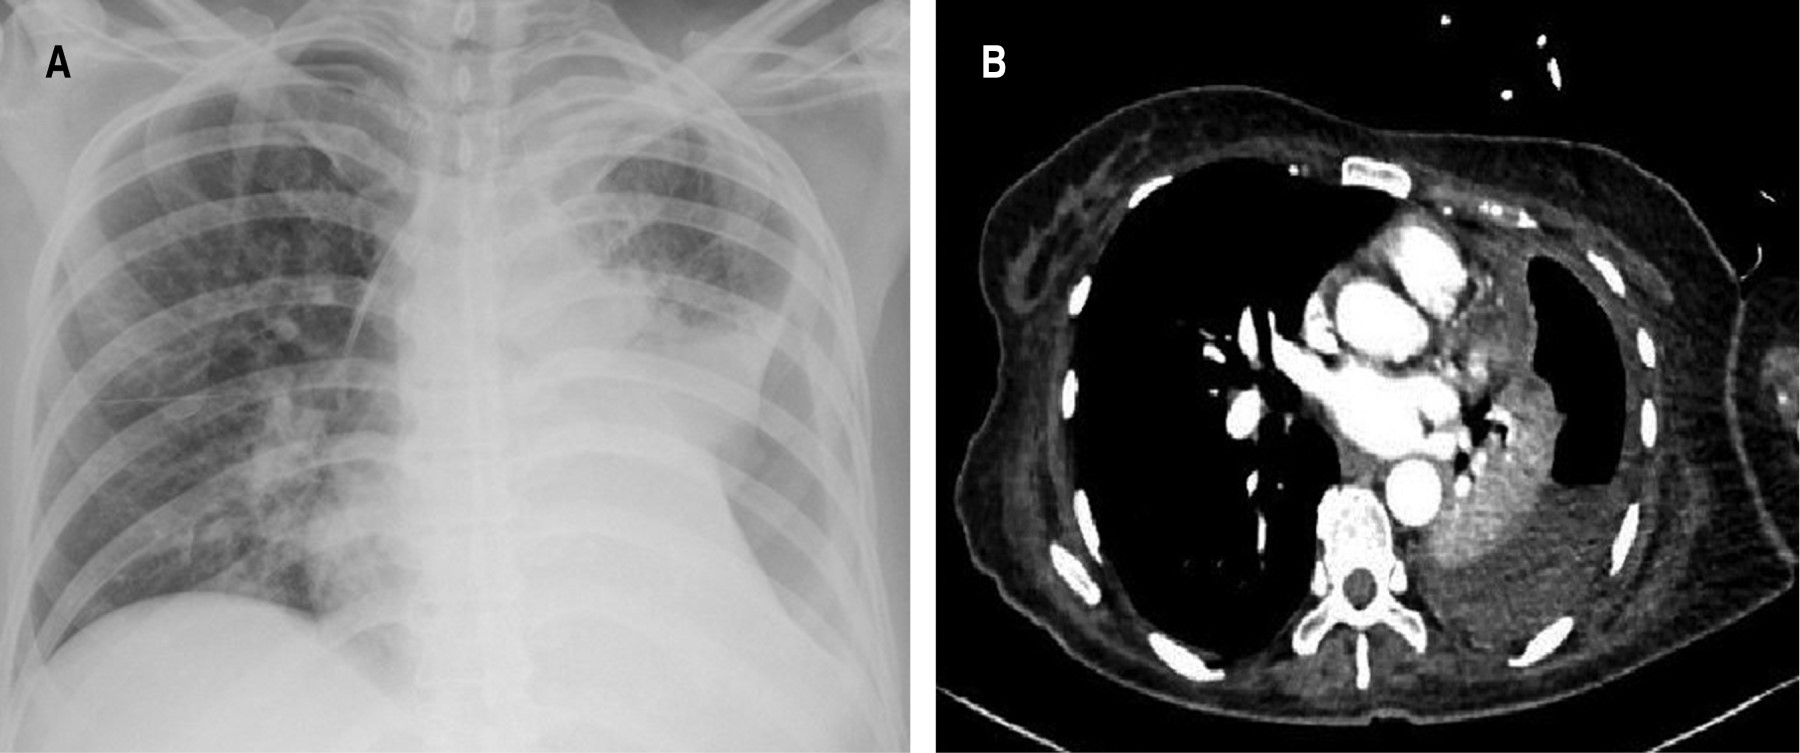

A su ingreso con TA 110/60 mmHg, frecuencia cardíaca (FC) 100 X', frecuencia respiratoria (FR) 30 X' y temperatura de 37.8 oC, saturación del 90%. En la exploración de tórax con ausencia de ruidos respiratorios basales derechos. Sin datos de irritación peritoneal con ligero dolor subcostal izquierdo. Se realizó radiografía de tórax con cavidad izquierda y tomografía de tórax que documentó empiema loculado con cavidad residual izquierda (Figura 1) y se decidió pasar a toracotomía para lavado y decorticación.